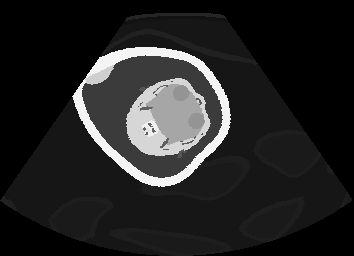

US simulation. We used a ray-tracing framework to render B-mode images from a geometric fetal model, by simulating a convex probe placed at multiple locations and orientations on the abdominal surface, with imaging settings listed in Tab 1. At each location, simply rasterizing a cross-section through the triangulated anatomical surfaces at the ultrasound center imaging plane provided corresponding semantic maps. Fig. 3 shows example B-mode images with corresponding semantic maps. A total of simulated frames were resized to and randomly split into training-validation-test sets by 80-10-10%.